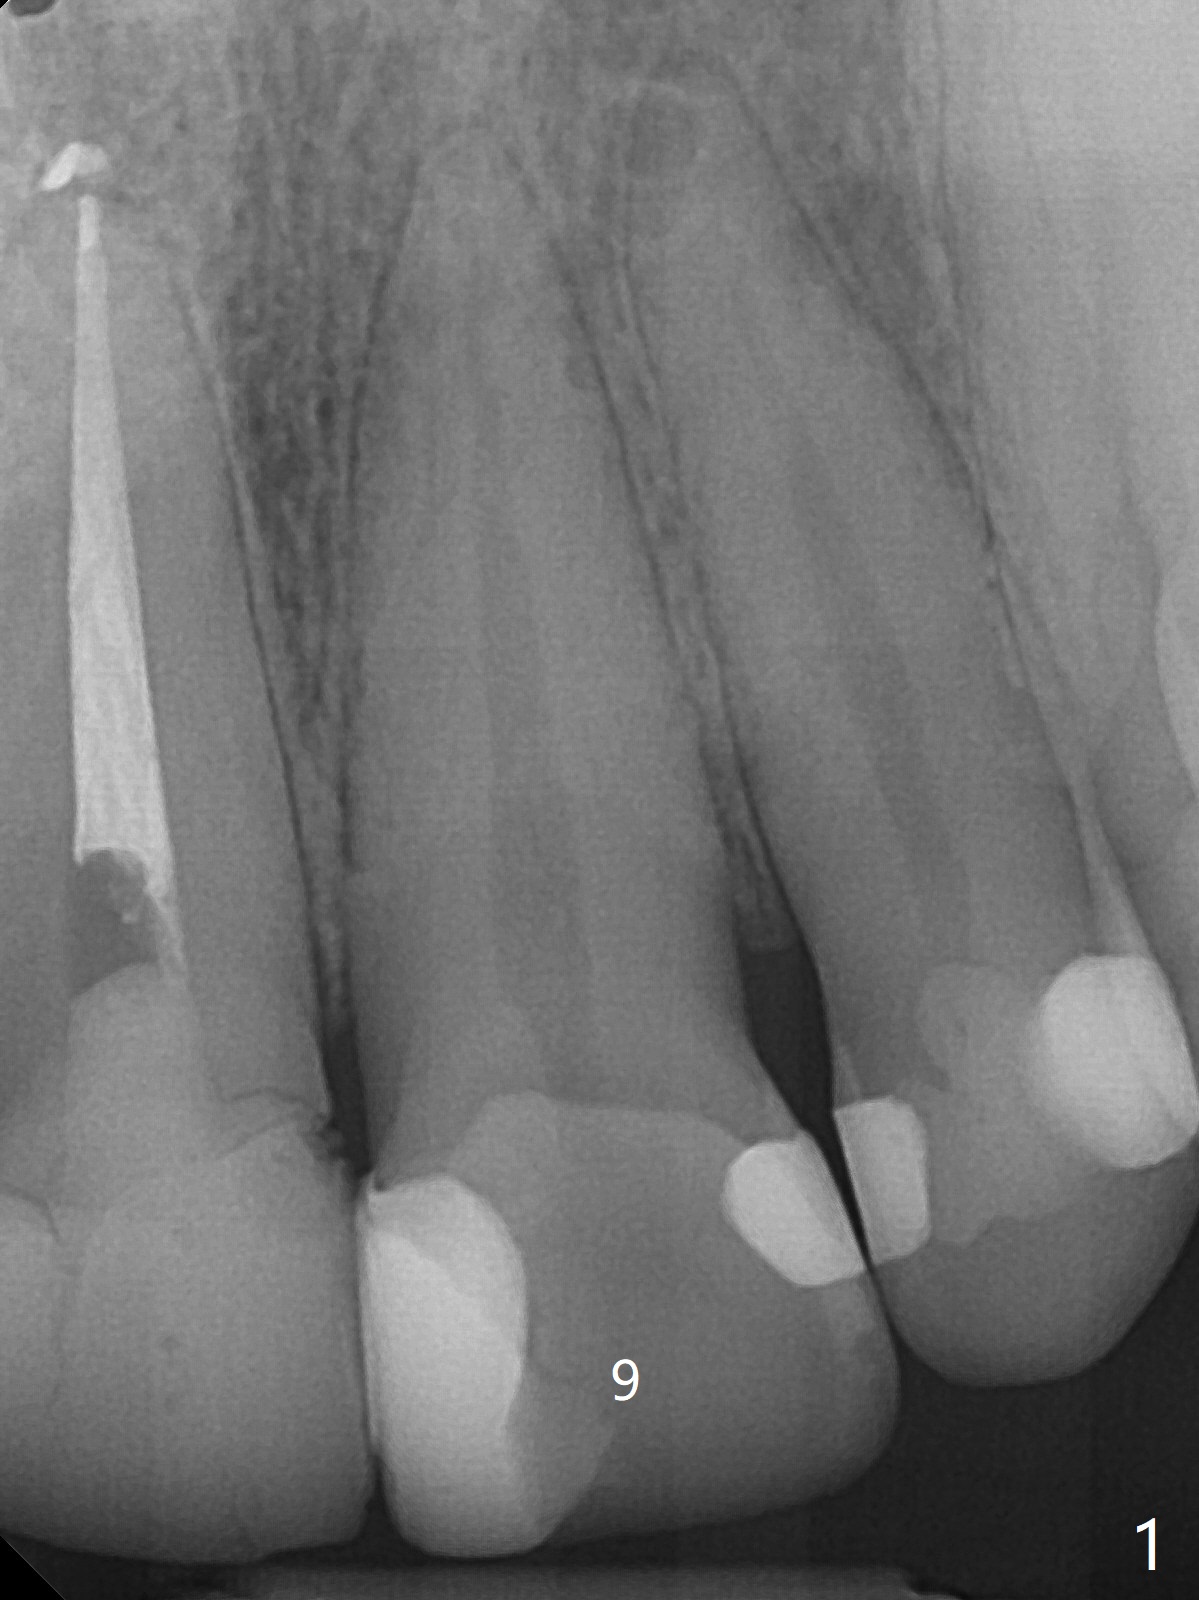

36岁女,9号牙树脂修补多次(图一),最近对冷热敏感,计划牙冠制备(如果不再敏感,再约一次与8号牙一起制备取模;如果敏感,9号牙根管治疗),使用Polycarbonate

Crown(图二,三)和Bosworth Trim II (Temporary Resin Acrylic

(D3)做内衬里)做临时牙冠。由于前者显得黄,而病人牙齿灰,她突然不满意,后来我们把临时牙冠表面磨掉,用Temporary